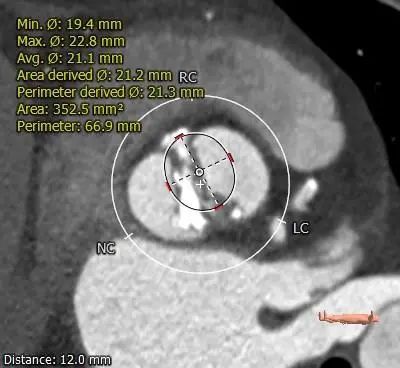

12mm SUPRA ANNULUS